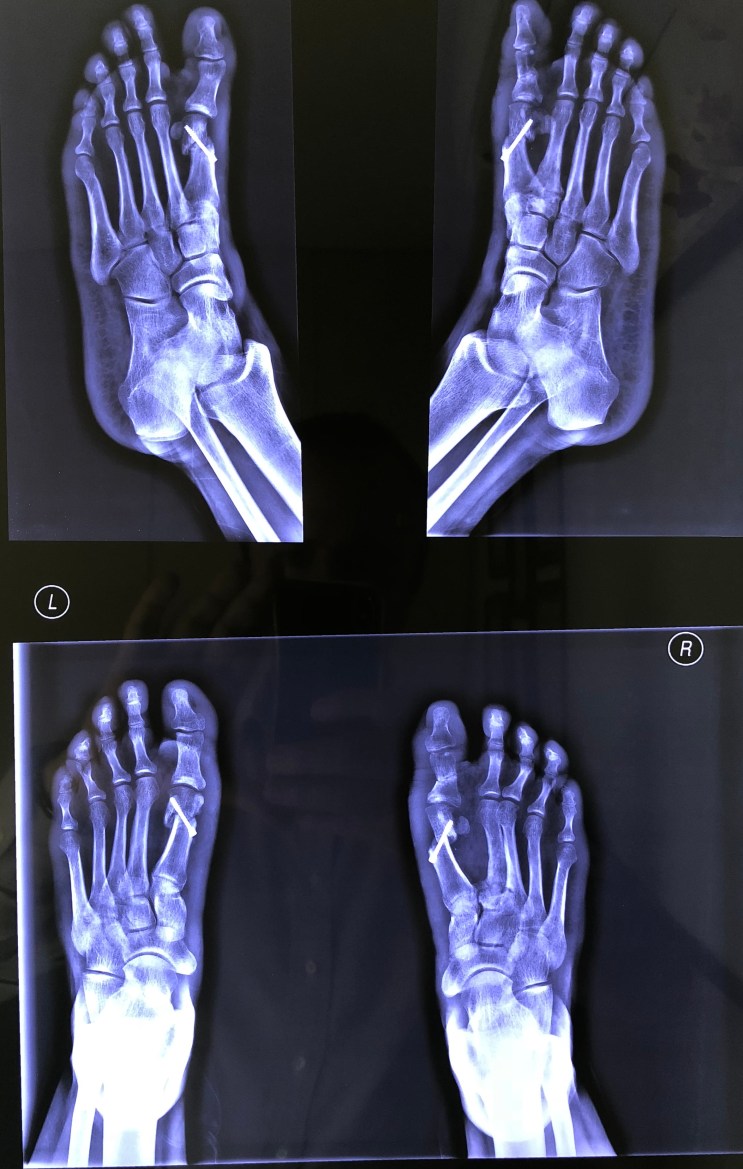

Upload Date: March 31, 2019 Full Size Image Dimensions: 2353 × 3705 Image Parent Post: ΧΕΙΡΟΥΡΓΙΚΗ ΚΑΤΩ ΑΚΡΟΥ

D.Μετεγχειρητικές ακτινογραφίες βλαισσών μεγάλων δακτύλων